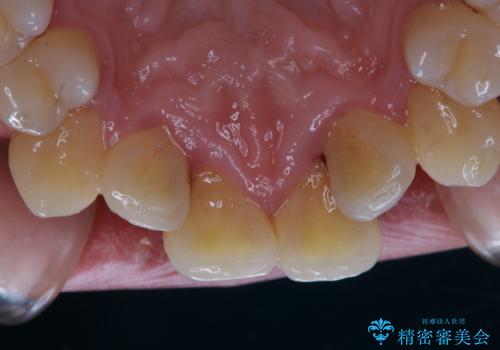

1年ぶりの歯医者でクリーニング

- 忙しく歯科医院でのメンテナンスが1年ぶりとのことで来院されました。PMTC60分コースを行いました。